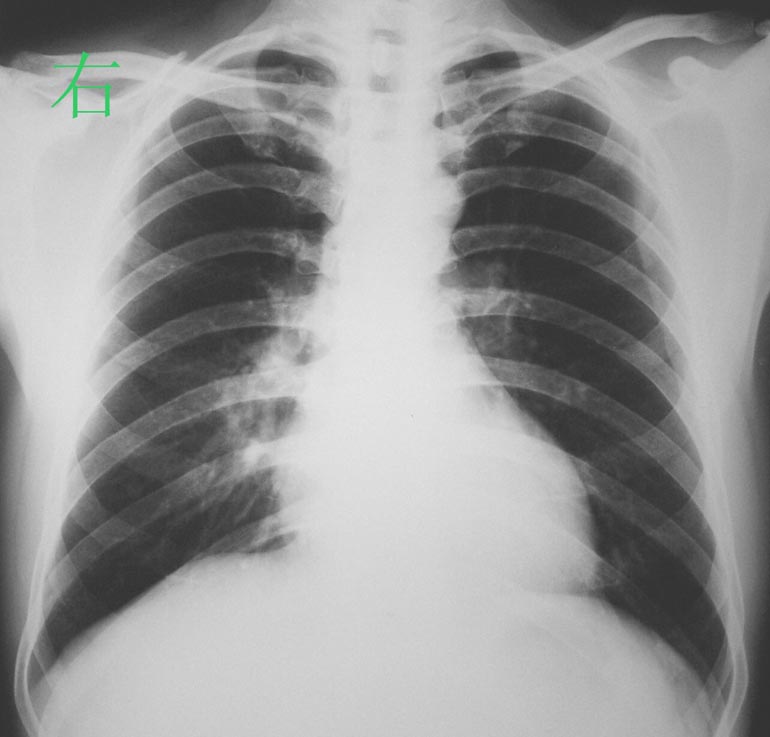

标题: X0288:右下叶背段肺脓疡

患者经抗炎治疗1个月病灶完全吸收。

最后诊断:右下叶背段肺脓疡。